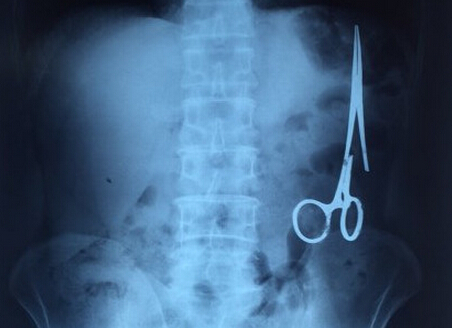

剪刀留腹中18年:X光顯示遺留在病人腹中的剪刀

醫務人員從X光片中看到,在病人腹部左側有一把剪刀,與結腸緊挨著。剪刀的把手已經生銹并且有一個把手已經爛斷了,患者的部分器官已經與剪刀粘連起來。

ct檢查顯示,M.V.N的腸子中有一把醫用剪刀。M.V.N證實,他曾于1998年6月份在北江省綜合醫院接受手術,在此后18年來從未進行過任何手術。近來,他感到腹部有些疼痛,并試圖通過服用藥物治療。